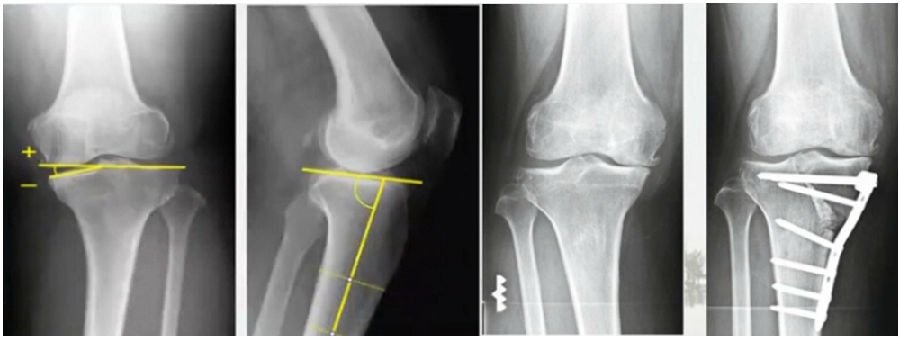

典型病例,女性,56岁,农民右膝内翻18度。

术前影像

术中影像

结合影像学来看,该患者单纯用闭合截骨或开放截骨,对肢体均有影响,所以决定采用混合型截骨。术中混合截骨旋转中心选在内外1/3处,先做闭合楔,然后顺势将开放楔敲开,达到术前设计的目标力线。术后随访力线达到要求。

术后X线